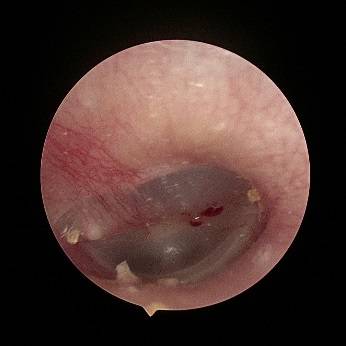

接诊的庞锋医师随即为该患者安排耳内镜检查 , 这一看吓一跳 , 小李耳朵里面竟然发现一只活蟑螂 , 这只蟑螂一直在耳道内活动 , 见到光照还拼命往里钻 。

蟑螂进入外耳道并导致外耳道皮肤损伤、出血